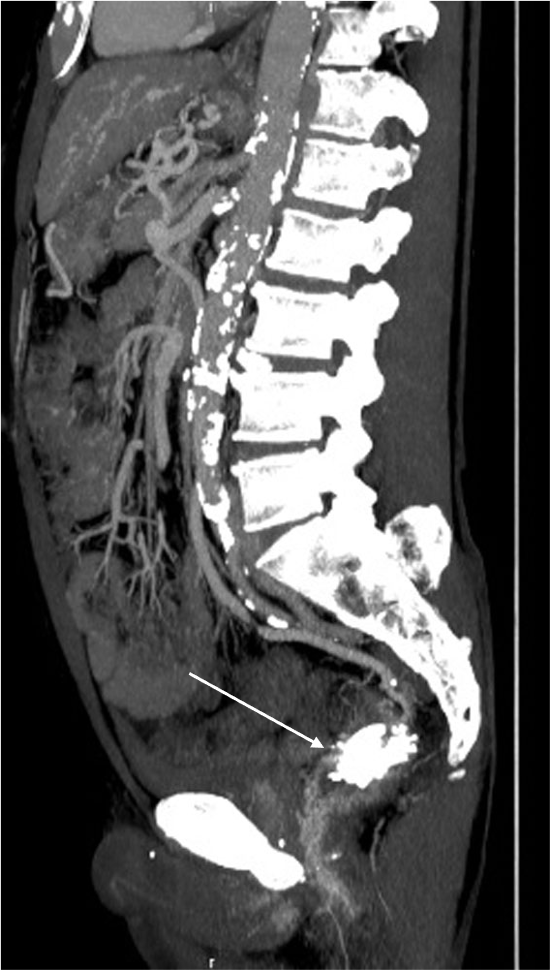

直腸静脈瘤の破裂予防目的にヒストアクリルを用いた経皮経肝的静脈瘤塞栓術を施行した。治療一か月後の治療効果判定に撮影を行った。

肝硬変のスクリーニング目的の造影CTにて直腸静脈瘤が判明した。破裂予防目的に経皮経肝的静脈瘤塞栓術を施行した。術前CTにて血管解剖を把握の上、治療を行った。術後一か月の造影CTにて、標的血管の良好な閉塞が確認された。

当該疾患の診断における造影CTの役割

直腸静脈瘤を始めとする異所性静脈瘤においては、IVR治療が選択されることが多い。術前に正確な解剖の把握が必要であり、造影CTの果たす役割は大きい。特に門脈系の良好な描出が求められ、適切な時相での撮影が肝要である。撮影後thin slice軸位断像での観察、任意多断面再構成像(MPR)やVolume rendering画像(VR)で評価を行い、術中のガイドとする。また肝細胞癌を併発することが多い為、動脈優位相における撮影も行う必要があり、dynamic studyを要する。治療においてはヒストアクリルや金属コイルなどのアーチファクト源となり得るデバイスが使用されるため、必要に応じてmetal artifact除去を活用する必要がある。また別部位に新たな静脈瘤が生じたり、腹水などの門脈圧上昇に伴う所見や門脈血栓などの合併症が生じる危険性があるため、造影CTによる評価が重要である。